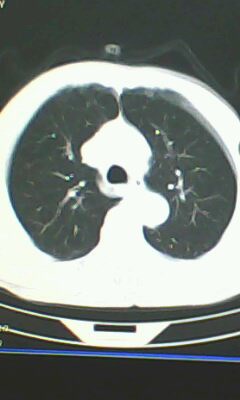

胸廓呈桶状,双膈低平,肺实质及纵隔未见明显异常密度灶考虑肺气肿.

肺气肿

以下是引用ctkz987在2010-5-5 21:30:00的发言:[br]胸廓呈桶状,双膈低平,肺实质及纵隔未见明显异常密度灶考虑肺气肿.

弥漫性肺气肿 但内胆管轻度扩张

临床诊断:copd

慢阻肺是临床诊断,未见明显异常。